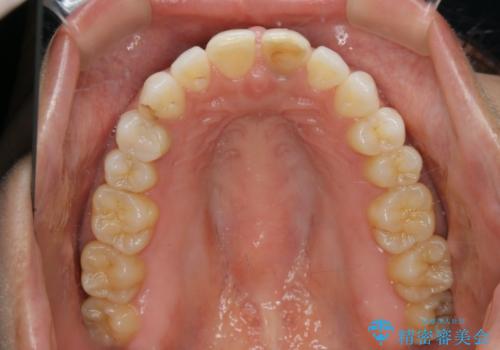

すきっ歯を治したい。インビザライン・ライトによる矯正治療

- 正中離開を気にされて来院された患者様です。

インビザラインでの治療を希望され、正中離開のみ治したいとのことだったので、インビザライン・ライト(片顎)での治療を選択しました。

インビザライン・ライトは枚数が少ないため歯の移動量に限界がありますが、短期間での治療が可能です。